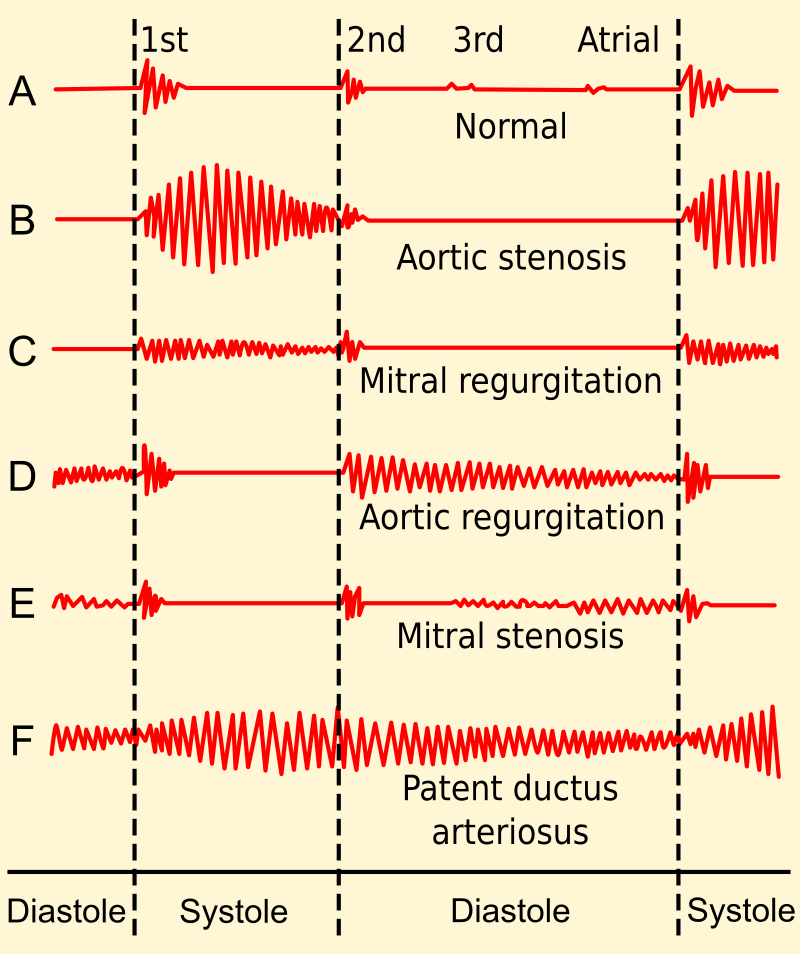

An atrial septal defect (ASD) results in a divided S2 and a left-to-right shunt on auscultation (increased blood in right heart delays closure of pulmonary valve).

Patent ductus arteriosus (PDA) is typically asymptomatic at birth with a holosystolic ‘machine-like’ murmur.